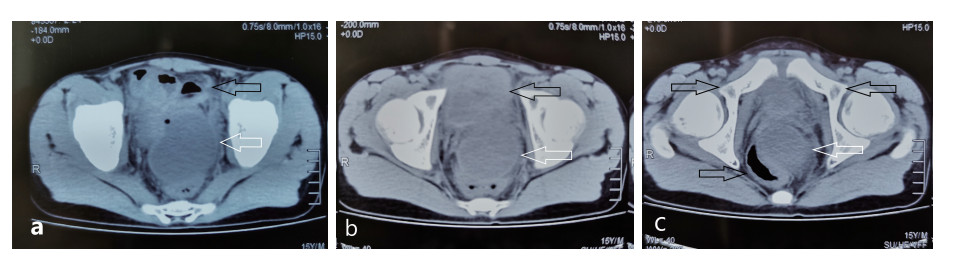

患者术后生命体征平稳,体温正常,引流管通畅,腹痛消失。术后3 d复查,血常规:白细胞6.73×109,中性粒细胞4.87×109;C-反应蛋白21 mg/L;降钙素原0.2 ng/mL;CT显示:盆腔可见引流管影,引流管周围未见明显积液(图 8)。脓液培养显示:大肠埃希菌。于术后4 d夹闭引流管,术后6 d拔除引流管,无明显并发症,顺利出院。术后6个月复查盆腔脓肿无复发。

| 图 8 术后腹腔CT显示:盆腔可见引流管影,引流管周围未见明显积液 |